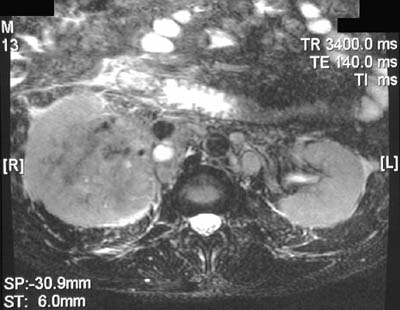

The axial MRI scans shown here reveal a renal cell carcinoma of the left kidney, seen with T1 weighting above and T2 weighting below.